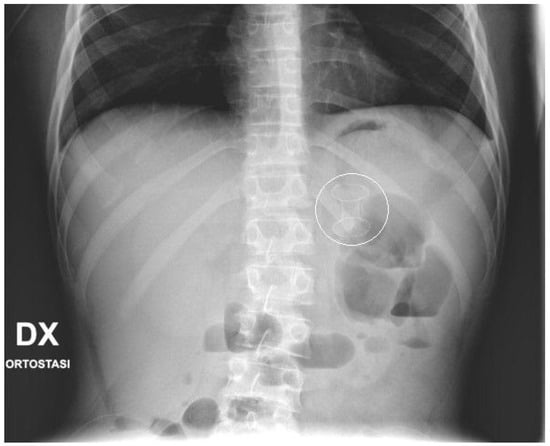

No fluoroscopy was needed during the position of the stent; nevertheless, an X-ray was taken at the end of the procedure (Figure 2). In the following days, the correct position of the stent was confirmed with bed-side US. In the patient with WON, endoscopic necrosectomy sessions was not performed. Post-operative treatment included adequate pain control, supportive care and early enteral nutrition, according to the clinical condition of the patients. Complications occurring after the procedures, such as perforation, bleeding, stent displacement, were carefully documented. The stents were kept in place until resolution of the PFCs, assessed with pre-operative routine echography and/or MRI. When indicated, the stents were electively removed by a simple esophagogastroduodenoscopy, performed as an outpatient procedure.

Figure 2.

Final X-ray. X-ray performed at the end of the procedure that shows the EC-LAMS as a radiopaque dumbbell-shape object projected in the epigastrium.